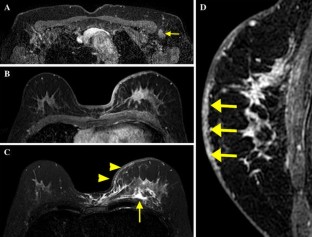

Fig. 4